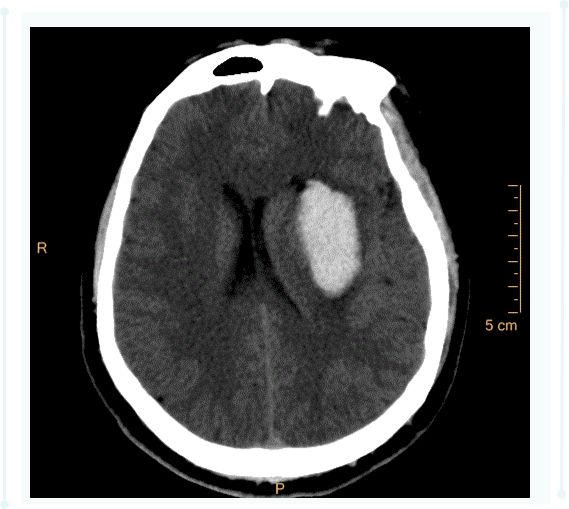

颅脑CT扫描 可清楚显示脑出血的部位、出血量大小、血肿形态、是否破入脑室以及血肿周围有无水肿及占位效应等。

急性期脑出血病灶多呈圆形或卵圆形均匀高密度区,边界清楚,脑室大量积血时多呈高密度铸型,脑室扩大。

脑出血 的CT表现典型,明确诊断非常简单。但是对于临床医生来说,脑出血患者进行CT扫描还有更多的需求:计算脑出血的出血量、明确脑出血部位等。